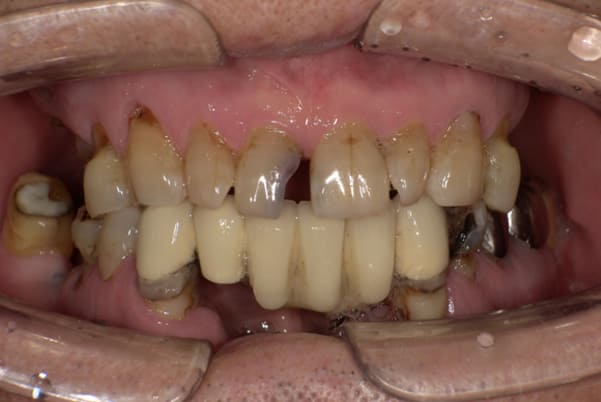

症例レポート[CASE.02]

- 男性(60代)

- 入れ歯がカパカパする、歯がぐらぐらして痛い、食いしばれない

- 上顎精密総金属床総入れ歯

- 下顎精密金属床部分入れ歯

上の前歯が重度歯周病により動揺し、残せない状態のため、入れ歯も動揺がありました。

ご自身の歯に負担の少ないバネ、また見た目も改善

バネをかける歯は繋げることで強度を増し、歯への負担を軽減し、歯の寿命を長くする設計へ。

バネがかかる歯の被せ物は、歯への負担を減らし、入れ歯が動きにくいようになる形態をあらかじめ付与することで、より入れ歯の機能が高まります。

治療を行う際、被せ物や入れ歯は、別々に考えるのではなく、一口腔単位としてお口全体のことを考え最良の治療計画を立てることが歯の寿命、機能効果を向上させるため、専門医としてこのことは常に心掛けて治療を行っています。

残りの歯に負担がかからないよう、被せ物と入れ歯の一体化を図った入れ歯

治療前は上下奥歯の入れ歯が削れていることで、かみ合わせが低くなり唇もつむった状態でした。

かみ合わせを適切な高さに戻したことで、本来の自然な口元へ。